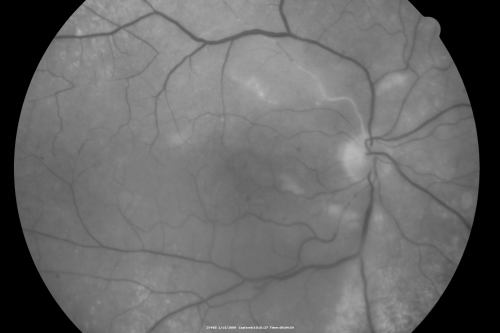

Bilateral Retinal Arteriol Occlusions - Possible Susac Syndrome

80-year-old woman one month ago had vision loss and a vascular occlusion in the right eye.  Vision loss occurred in the left eye about 9 years ago with cotton wool spots.  Patients has a 30 year history of tinnitis.